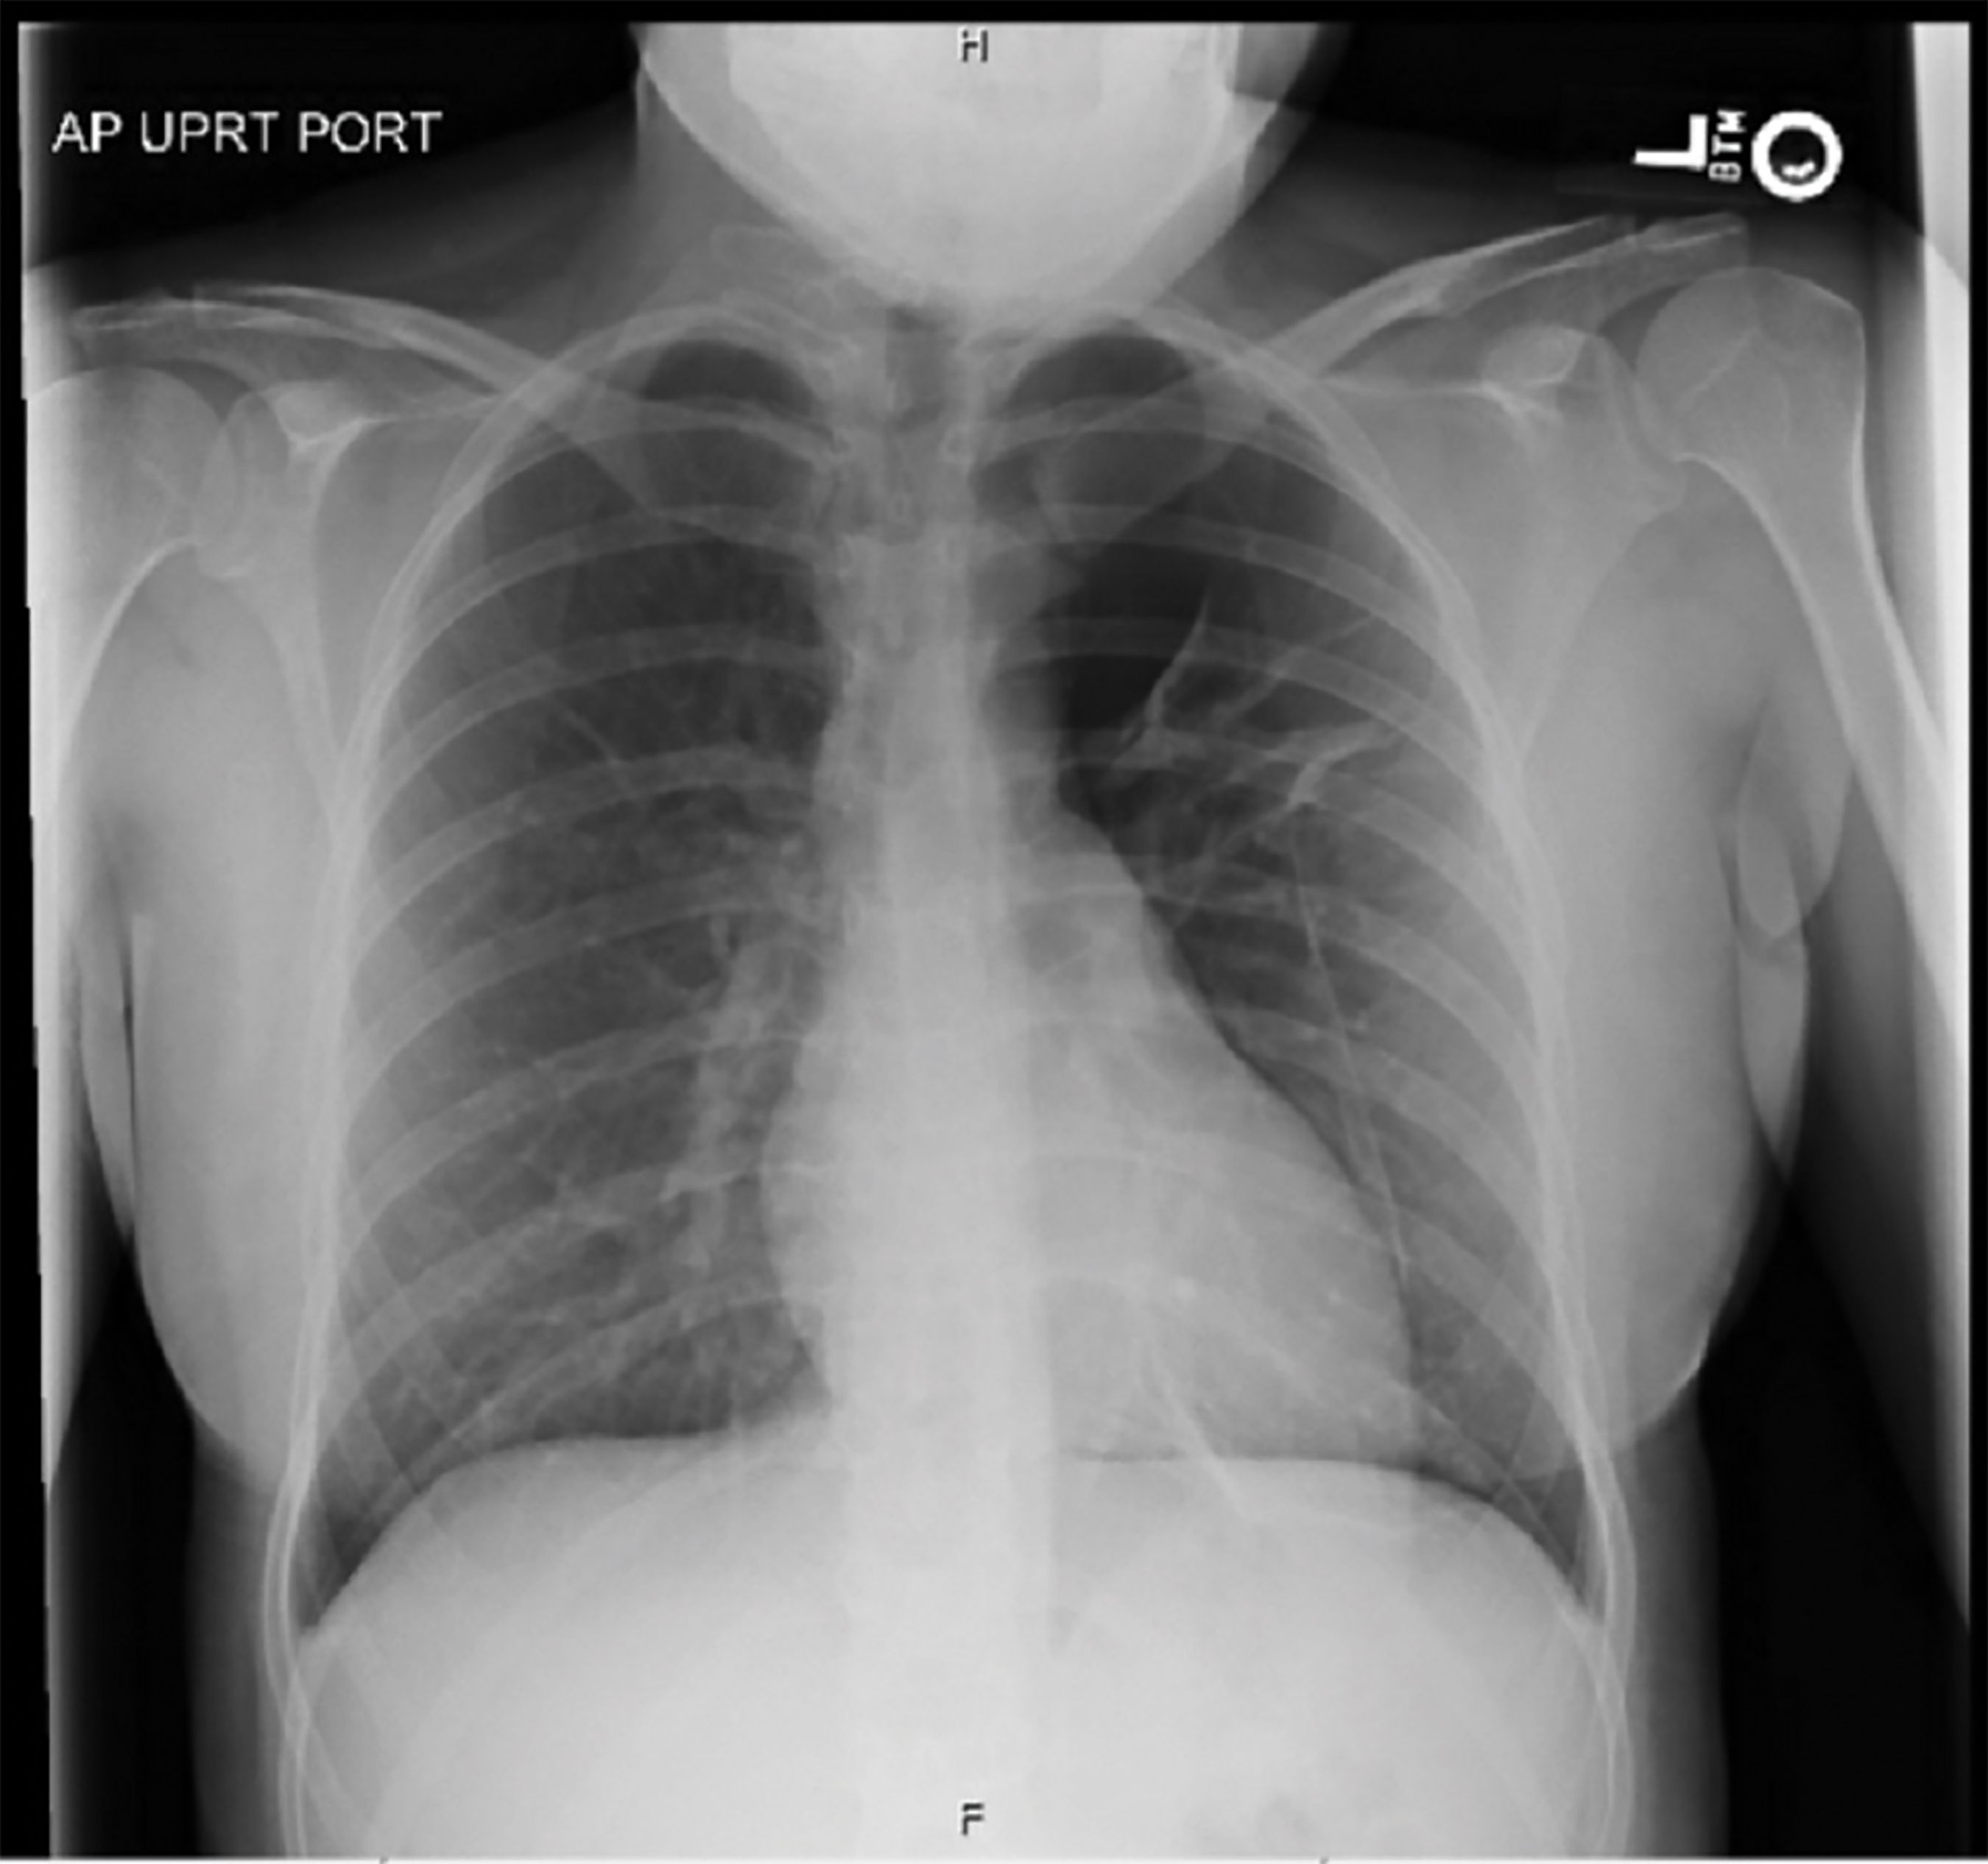

Laboratory evaluation included complete blood cell count with di fferential, D-dimer, and basic metabolic panel, all of which were within normal limits. Serum lithium level was subtherapeutic at 0.3 mg/dL. A urine drug screen was not obtained. A chest x-ray revealed a moderate to large left apical pneumothorax, unremarkable cardiomediastinal silhouette, and no consolidation or effusion.

Two days after admission, the patient developed worsening pain and shortness of breath. A repeat x-ray showed the size of pneumothorax had increased (Figure). Despite a pigtail catheter chest tube placement, the pneumothorax persisted, and she required video-assisted thoracoscopic surgery (VATS) with left apical blebectomy, mechanical pleurodesis, and dual left side chest tube placement. The postoperative course was uncomplicated. Patient was discharged home on postoperative day 2 following chest tube removal. Gabapentin was added for pain control on discharge. The resected lung tissue specimen was sent for pathological examination.